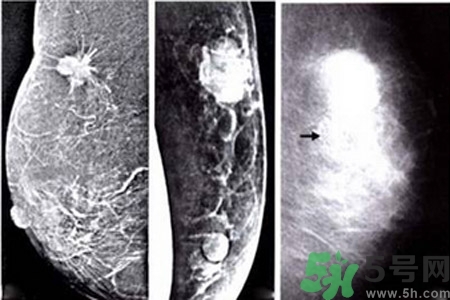

乳腺增生鈣化是乳腺癌常見的影像學(xué)表現(xiàn)之一。某些特異形態(tài)的乳腺增生鈣化是乳腺癌的危險(xiǎn)因素,統(tǒng)計(jì)資料表明65%的乳腺癌有鈣化,其中70%為惡性鈣化。

早期乳腺癌唯一的X線征象

成簇樣微小鈣化常是早期乳腺癌唯一的X線征象。根據(jù)微小鈣化形態(tài)、大小、數(shù)量和密集度等表現(xiàn)可反映病變性質(zhì)和范圍。微小鈣化點(diǎn)可位于腫塊內(nèi)或周圍,總數(shù)目6~15枚,密度不均,大小不等。